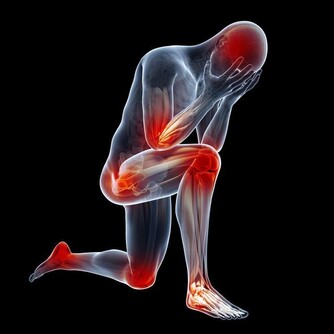

6、關節攣縮:腦梗塞病人如果沒有得到良好的康復訓練,患側的肌肉會發生廢用性萎縮,在肌肉萎縮和張力升高的共同作用下,關節長期不能正常活動,會造成病人關節畸形、攣縮。患處的關節活動會變得很疼痛。